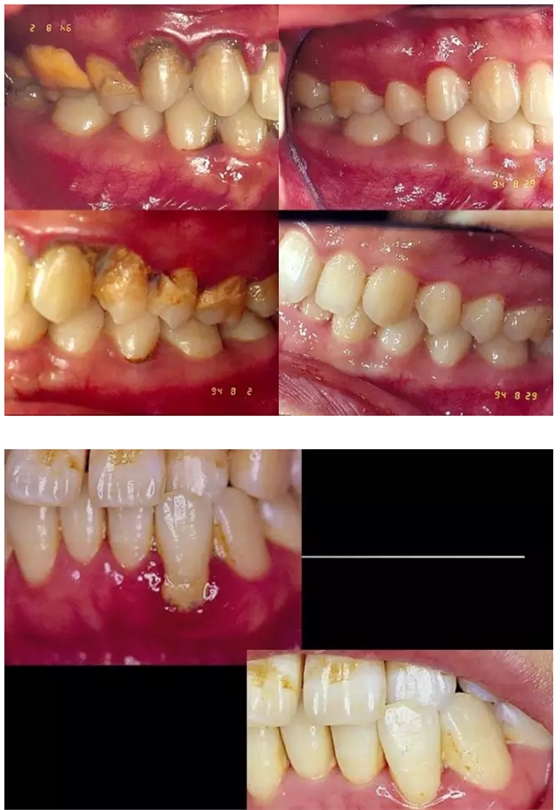

【牙科知識(shí)】牙周病相關(guān)手術(shù)圖解,非醫(yī)學(xué)專業(yè)勿點(diǎn)